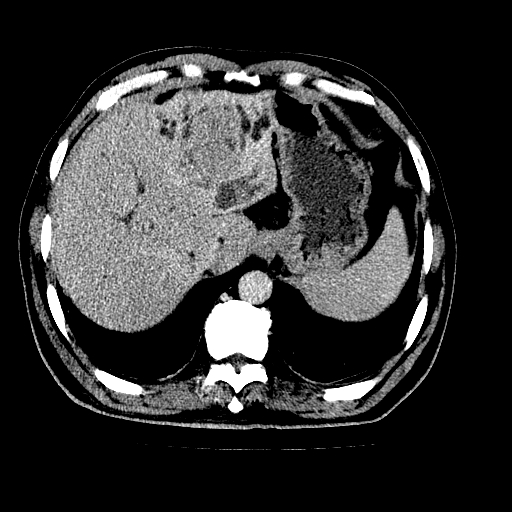

男,66岁,上腹部不适、黄染一周。彩超示:肝左叶占位,肝内胆管扩张,胆总管扩张,胆总管占位?

肝左叶不规则软组织肿块影,边缘不规整邻近肝实质受累分界不清;肝内胆管(左叶)明显扩张成“软藤状”,诊断:肝左叶胆管细胞癌。

肝左叶不规则软组织肿块影,边缘不规整邻近肝实质受累分界不清;肝内胆管(左叶)明显扩张成“软藤状”,诊断:肝左叶胆管细胞癌。胆囊钙乳症。

胆囊缩小,其内胆汁浓缩,也提示梗阻部位应该位于胆囊管起始部以上或是胆囊管受累及,支持肝外胆管癌。